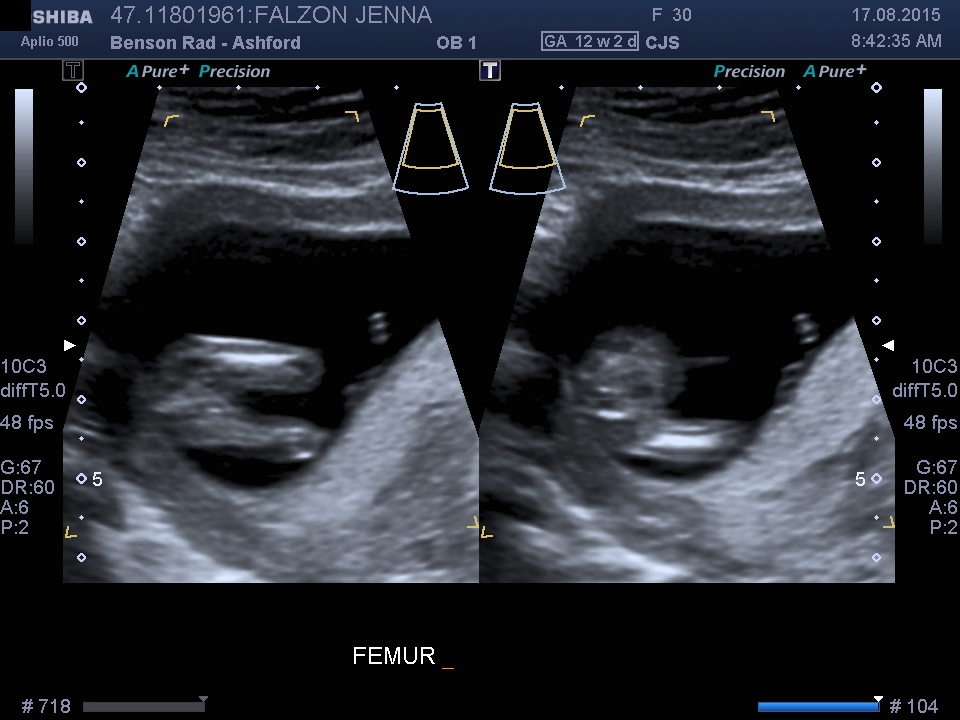

Thanks, no unfortunately didn't get any shots with the nub

Maybe girl. Without profile shot of the nub, it's hard to say.